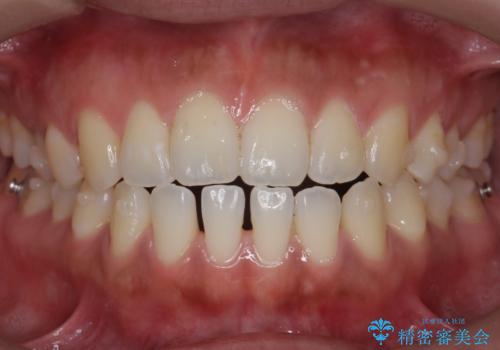

受け口、すきっ歯を インビザラインで モニター治療

- 前歯のすき間と受け口を気にして来院。

マウスピースでしっかり閉じています。

下の前歯を後方に移動するため、ゴムを上下のマウスピースにかけてもらいました。